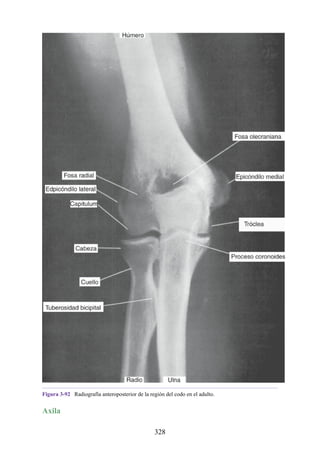

Revisión

Columna vertebral